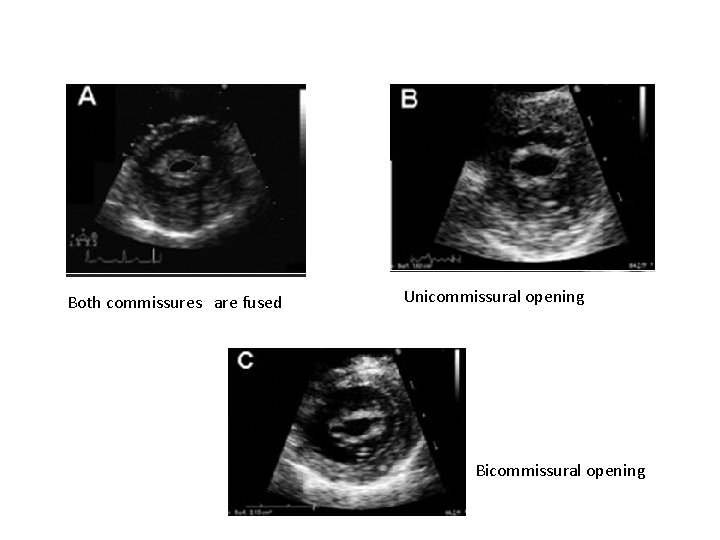

2 D ECHO § Commissural fusion Assessed in PSAX view Rheumatic etiology Complete fusion - severe MS. § Leaflet thickening Asssessed in PLAX § Chordal thickening & fusion in PLAX , Apical 4 Chamber views

Both commissures are fused Unicommissural opening Bicommissural opening

Advantages of planimetry Ø Direct measurement of MVA. Ø Does not depend on flow conditions, cardiac chamber compliance or associated valvular lesions. Ø Best correlation with anatomic valve area of explanted valves. Disadvantage Ø Not feasible in poor acoustic window and severe valve calcification.